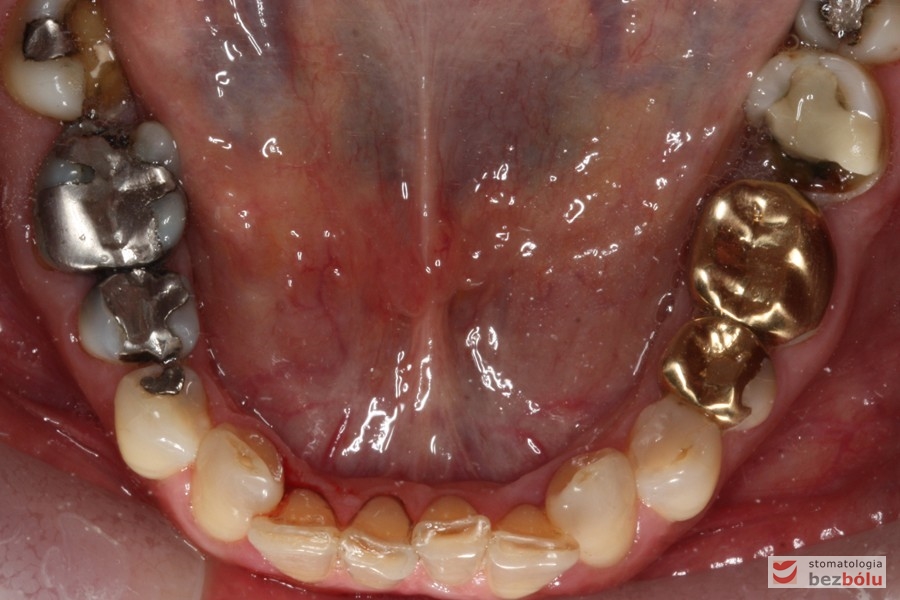

Do naszej placówki zgłosiła się starannie planująca swoje działania Europejka, mieszkająca na stałe w Kotlinie Jeleniogórskiej. Jej oczekiwania dotyczyły bardzo metodycznie zaplanowanego planu leczenia. Celem jaki postawiła przed naszym zespołem lekarzy było wyeliminowanie wszystkich wątpliwych i nierokujących wypełnień, a także poprawa estetyki w zakresie lewego siekacza centralnego w szczęce. Został rozpisany blisko dwuletni plan wymiany zużytych i nieszczelnych wypełnień amalgamatowych i kompozytowych. Zaplanowano również przygotowanie endodontyczne wybranych zębów w szczęce i żuchwie, a także zaopatrzenie w inlay’e porcelanowe i korony ceramiczne wykonane w systemie e-max.